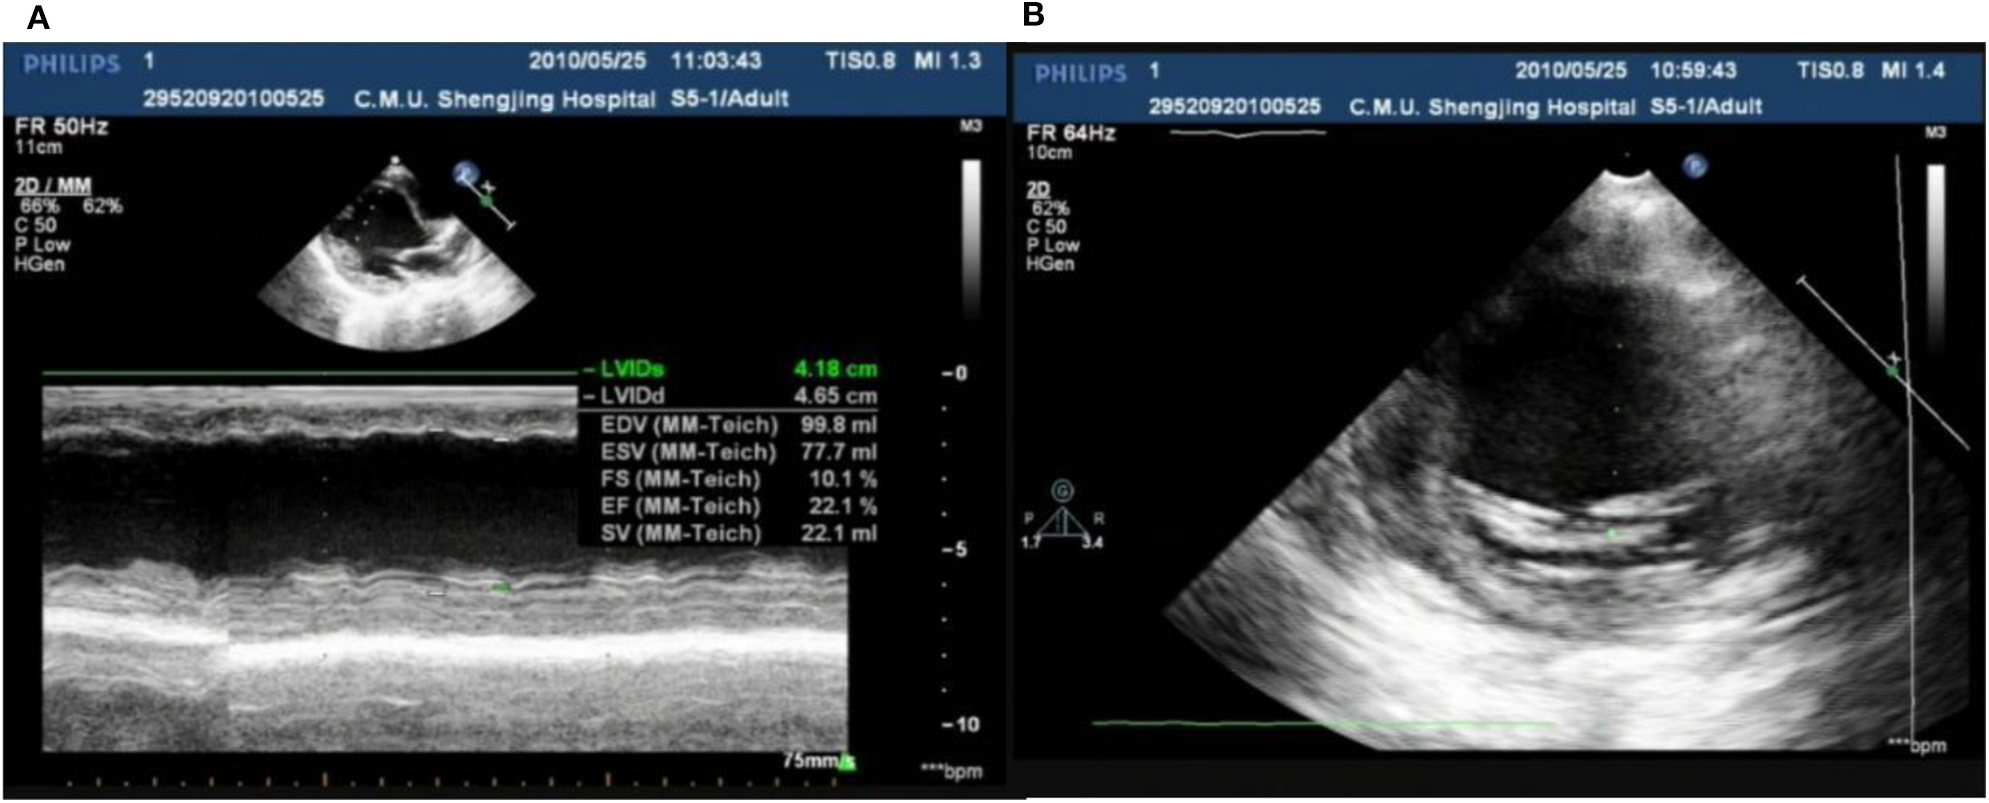

In our center, there were two cases of neonatal onset of SVT, presenting with normal QRS complex, increased LVED, and nearly normal cardiac function at the initial diagnosis. Three WPW cases were enrolled in our study, one (Case 1) (Figure 8) merits further description. She did not undergo radiofrequency ablation upon WPW diagnosis, and had significant cardiac dysfunction (LVEF = 0.22) (Figures 9A,B) in 2010. At that time (when she was 18 months of age), there was a lack of understanding of WPW associated cardiomyopathy and few hospitals in China carry out radiofrequency ablation for infants. It was commonly accepted that radiofrequency ablation in young children was associated with a risk of valve damage (20). We did not discuss fully radiofrequency ablation with her parents, and she was not followed up after discharge for economic reasons until her worsened cardiac insufficiency at 6 years of age (LVEF = 0.18). At this point, we explained the prognosis as well as the necessity and possible risks of radiofrequency ablation to her parents. Her parents decided on conservative treatment instead. She died at the age of 8 years, more than 6 years after her initial examination.

Figure 9

Echo showed LVED 46.5 mm, LVEF 0.22 (A); endocardial thickness 3.5 mm (B) in case one at her 2 years old.